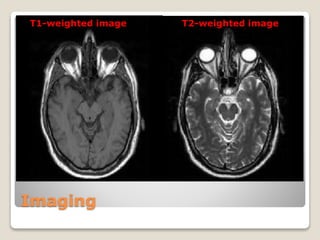

MRI

T1W images T2W images

T2-weighted imageT1-weighted image